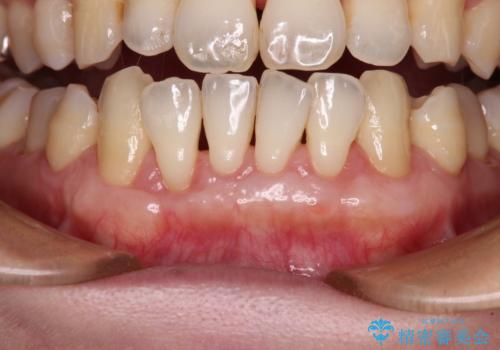

- 年々歯肉退縮が進行することを気にして来院された患者様です。

歯肉が菲薄であることが経年的な進行の原因であることが推察されたため、上顎からの結合組織移植術(CTG)により、歯根の被覆を行うとともに、歯肉の厚みを増すことで将来の退縮リスクを抑制することとしました。

上顎両側から歯肉を採取したたため、術後は痛みや出血で辛い思いをされましたが、1回の処置で満足のいく結果となりました。

根面被覆量も改善できましたが、歯肉の厚みが十分なものとなったことで、今後の歯肉退縮に歯止めをかけることができました。